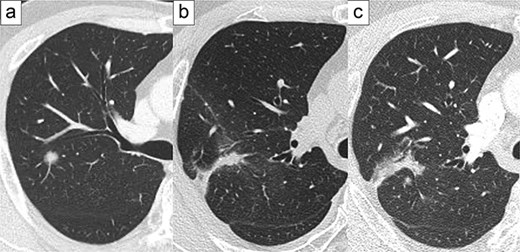

A 58-year-old male smoker with a 9-pack-year history was referred to our hospital due to suspicion of a second lung cancer recurrence. He underwent cryoablation for cT1N0M0 stage IA1 lung cancer at 52-year olds (Fig. 1a) and again because of local lung cancer recurrence at 56-year old (Fig. 1b). Chest computed tomography showed a progressively enlarging infiltration in segment 2 (Fig. 1c). A second local recurrence of lung cancer was diagnosed and robotic portal right upper lobectomy and mediastinal lymph node dissection were performed. Preoperative chest computed tomography with 3D image reconstruction also revealed a partial anomalous pulmonary venous return; V1–3 drained via the azygous vein into the superior vena cava, and the upper pulmonary vein did not drain into the left atrium.

Representative images of preoperative computed tomography. Primary lung cancer at the age of 52 (a), first local recurrence at the age of 56 (b), and second local recurrence at the age of 58 (c).